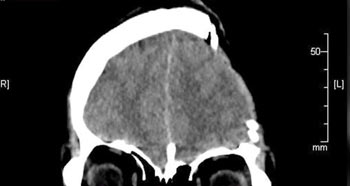

• ▲頭蓋骨の左側の除去手術を受けた後のウ・ウンビンさんのレントゲン写真。/MBC『心臓を鳴らせ 講演者たち』

脳出血と脳浮腫が見られ、左脳の95%が損傷した。左の耳と前頭葉の下に血があふれ、嗅覚と神経細胞も損傷した。手術の執刀医は家族に対し「生存確率は20-30%程度」と伝え「生きられたとしても30代女性としての健康な人生を送るのは難しいでしょう」と話した。それを聞いた家族は、とにかくウさんが生きてさえいてくれればいいと祈ったという。

頭蓋骨の左部分を5分の2ほど除去する手術を受けたウさんは、左脳の損傷が原因で言語障害が残った。医師は家族に「また幼い子どもに戻ったと考えてください」と話したという。実際にそうだった。ウさんは「車」「サンドウィッチ」など幼児でも分かるような単語を口にすることができなかった。ウさんは「何か話したいのに話すことができない自分自身がとても嫌だった」「そんな自分を認めたくなかった」と話した。